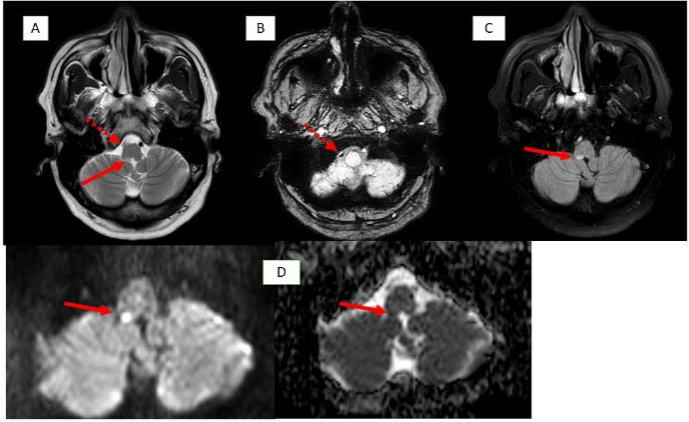

Methods: Two male patients presented with persistent hiccups, nausea, and vomiting. Imaging confirmed lateral medullary infarcts involving the area postrema. Etiological investigations included vascular imaging and thrombophilia workup.

Ischemic Area Postrema Syndrome (APS) is a rare neurological condition characterized by persistent nausea, vomiting, and hiccups resulting from an infarction in the area postrema, a highly vascularized, circumventricular structure in the dorsal medulla. Supplied by small perforating branches of the anterior spinal artery or vertebral artery, this chemoreceptor “vomiting center” lacks a typical blood–brain barrier, making it uniquely vulnerable to ischemic injury. Although ischemic stroke is an infrequent cause of APS, case reports—highlighting dorsal medullary infarcts confirmed on thin-slice diffusion-weighted MRI—demonstrate that small, localized ischemic events can disrupt the area’s function and induce classic APS symptoms.

| MRI Findings | Acute lateral medullary infarct (right area postrema), loss of normal flow void in right vertebral artery and PICA → intraluminal thrombus | Infarct in lateral medullary area, thrombus in right vertebral artery, T2 hyperintensities in bilateral cerebral hemispheres perpendicular to corpus callosum |

Early recognition of APS is crucial for timely diagnosis. In NMOSD, APS can precede MRI findings, warranting early immunotherapy. In contrast to stroke, APS in NMOSD is driven by autoimmune astrocytopathy, where anti-AQP4 IgG binds to astrocytic water channels in the area postrema, triggering complement activation and resulting in astrocyte loss, immunoglobulin/complement deposition, and inflammatory infiltrates. In a stroke, infarction leads to irreversible damage. Ischemic-stroke-induced Area Postrema Syndrome (APS) results from vascular occlusion—typically of perforating branches from the anterior spinal or vertebral arteries—leading to neuronal ischemia, necrosis, and microglial activation within the dorsal medulla, as demonstrated by diffusion-weighted MRI in case reports.